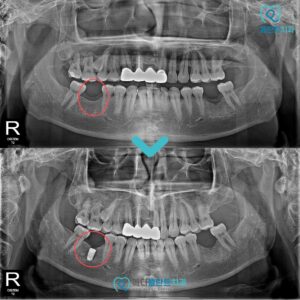

이를 위해 본.원에서는

3D CT와 구강 스캐너를 활용하여

구강 구조를 정밀하게 분석하고

개개인의 상태에 맞는 맞춤형 치료 계획을 수립합니다.

특히 뼈가 부족한 경우에도 골이식술을 병행하여